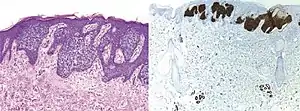

Comparison H&E stain (left) with BerEP4 immunohistochemistry staining (right) on a pathological section having BCC with squamous cell metaplasia. Only BCC cells are stained with BerEP4.[1]

Comparison H&E stain (left) with BerEP4 immunohistochemistry staining (right) on superficial BCC pathological sections mimicking Bowen’s Disease.[1] At bottom, columnar epithelium in normal sweat glands stain positive too.